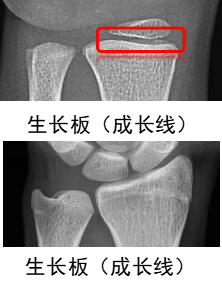

1.什么是骨龄?

人的生长发育有两个“年龄”:生活年龄(年纪)和生物年龄(骨龄)。骨龄就是指骨头的年龄,每个阶段骨骼的成熟度都不同。骨龄可真实地反应儿童的生物年龄,根据骨龄可客观地评价儿童生长发育水平,一般通过儿童的左手正位X光片来评估。想让孩子有一个理想的成年身高,应尽早定期检测骨龄,并进行身高体重管理。